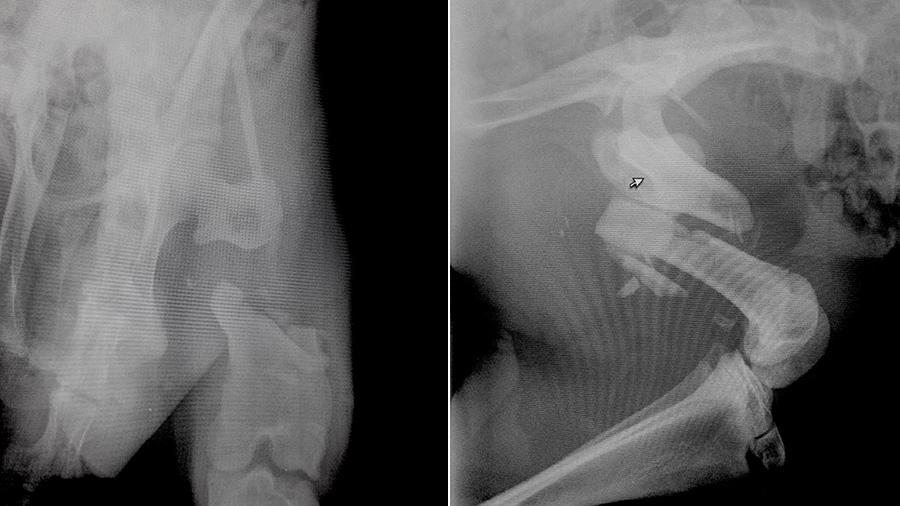

“This young kangaroo had just been acquired by a safari adventure park in Italy and the park’s veterinarian sent it to the hospital where I was working in 2015. The poor thing suffered from a comminuted fracture of the femoral shaft extending from the subtrochanteric region to the distal femur,” he explained. “The park owner wasn’t too convinced to let us try to fix the patient because he was told there was no way to successfully treat the fracture. But I was keen to do something about it and Matteo, the park’s vet, was very convincing with the owner. The hospital staff could not stop taking pictures as the patient was like a big, funny mouse!”

The challenges were many and they had to be taken seriously. First, there was no time to find sources of anatomical reference for red kangaroos in the medical literature. Surely, they existed with an accurate search, but the clock was ticking. Second, anesthetizing a kangaroo is not a straightforward procedure, a factor that had to be taken seriously as a mistake could have jeopardized the patient’s life or resulted in serious harm to the surgical team, given the animal’s powerful and potentially lethal hind quarters.

“I knew I could fix the bone but I was concerned because I could not gather enough information regarding the approach. I did a quick Internet search but I found no references in the literature and this fracture needed to be fixed as soon as possible, considering the huge muscles involved and the possibility for dramatic contracture that would have made the reduction impossible or even a compartment syndrome,” he said.

Using an intramedullary pin associated with double locking plates (rod and plate configuration) the fracture was bridged without an attempt to achieve perfect anatomic reduction but just focusing on the correct alignment.